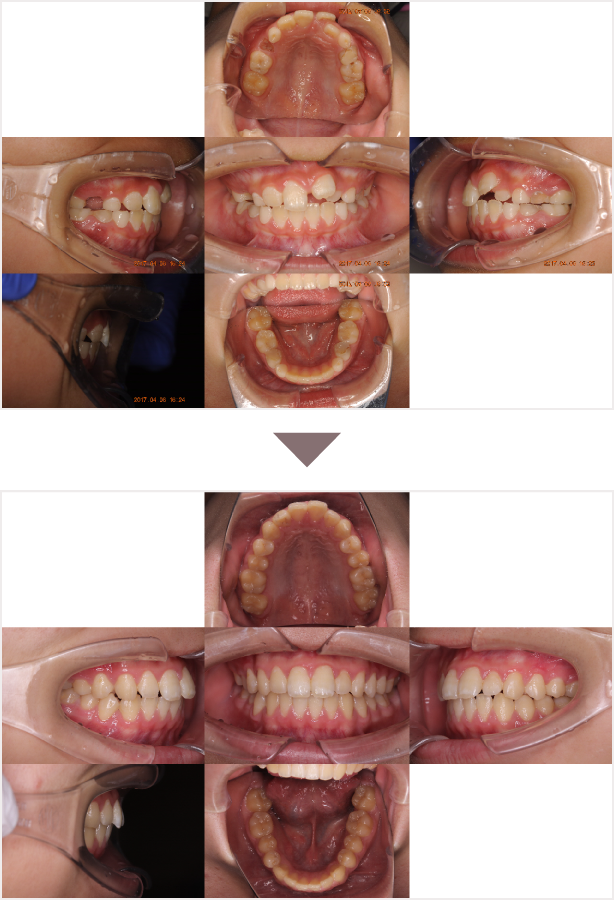

症例叢生

性別

期間8年8ヶ月

治療内容N-Bimler装置、Neo-Capを使用して治療

治療における

副作用・リスク

装着しないと効果は出ません

金額ビムラー装置:550,000円

ネオキャップ:4本

合計:572,000円